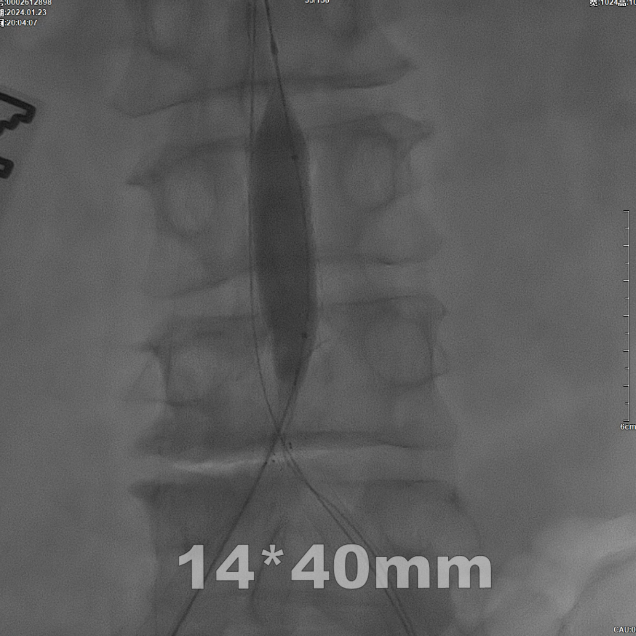

CERAB技术的关键点一:经双侧股总动脉植入2枚VBX球囊扩张式覆膜支架(8L×79mm),与腹主动脉覆膜支架腔内平行放置,且两枚支架端平齐对接。

CERAB技术关键点二:先用14mm×40mm球囊分别扩张双侧髂肢的腹主动脉段。

再用8mm球囊对双侧髂支腹主动脉段行对吻扩张,以确保双侧髂支与腹主动脉覆膜支架腔内获得良好的贴壁形态,最大程度减少空腔,降低远期再狭窄发生率。